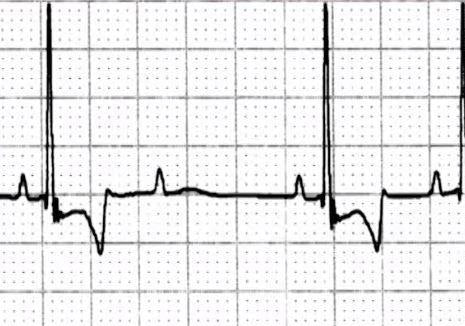

Atelier d'interprétation d'ECG (la partie 2)

D'Interprétation d'ECG Atelier (Partie 1)